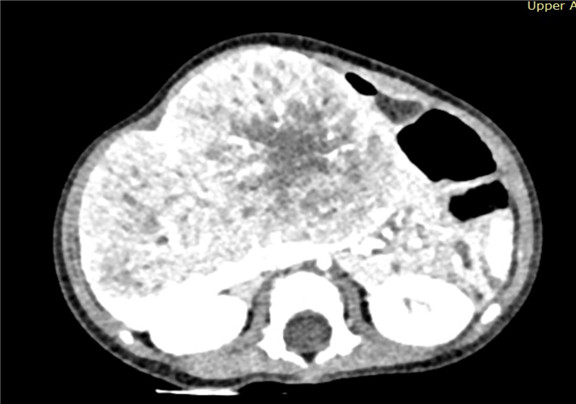

上腹部增强CT:肝脏占位性病变,疑似肝母细胞瘤,或血管母细胞瘤.

术前CT检查:

动脉期

静脉期